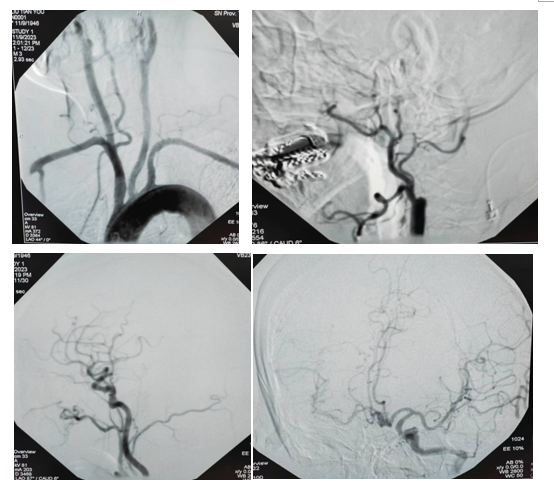

经惠振亮、阮绍萍、王宏主任医师认真评估后,认为患者“脑梗死、脑动脉狭窄”诊断明确,存在进一步脑血管造影检查适应症,与患者及家属沟通后,完善术前相关检查,无明显禁忌症,于2023年11月09日13:00在我院导管室,局麻下行脑动脉造影术,术程顺利,术后患者安返病房。

DSA结果提示:左侧颈总动脉及左侧锁骨下动脉,各血管起始部无异常,右侧锁骨下动脉远端未显影,右侧椎动脉粗大,左侧椎动脉未显影。右侧侧椎底动脉及其分支血管正常,后交通开放,右侧大脑中动脉区域血管显影;右侧颈内动脉起始部闭塞,远端未显影。左侧颈总动脉造影见左侧颈内动脉起始段正常,左侧大脑中、大胶前动脉及其分支血管正常,前交通开放,右侧大脑前动脉及其分支血管正常,右侧大脑中及其分支血管显影,但血管相对较细。

造影的结果为患者下一步的治疗及预后提供了可靠的证据,同时也开创了神经内外科融合发展、探索多学科协调合作的路子,能更好地服务于患者。